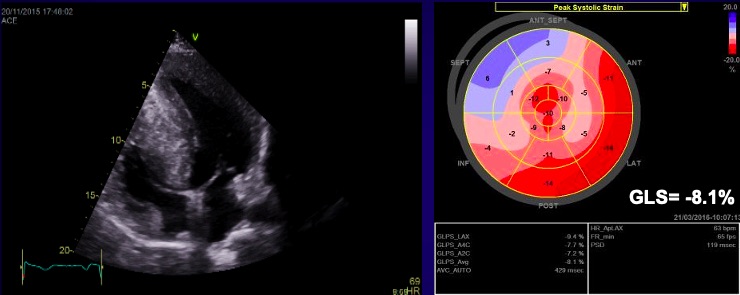

The most specific feature of the myocardium in HCM is the reduced contractile stress (the force per unit area) because of the cardiomyocyte disarray and interstitial fibrosis [33, 37]. A maintained ejection fraction is explained by the increased end-diastolic wall thickness that produces an augmented thickening, but the histopathology of this disease is characterized by myocardial hypertrophy, fiber disarray, increased loose connective tissue, and fibrosis, which are all thought to interfere with force generation and relaxation of the cardiac muscle. Both speckle tracking and tissue Doppler highlight this feature, with a significantly lower longitudinal systolic strain, systolic strain rate, and early diastolic strain rate (see Fig. 7) [27, 28, 30, 37]. GLS is independently associated with outcomes in HCM patients. A GLS with a value higher than –10 percent is associated with a higher risk of adverse events. This depressed contractility function of the LV correlates also with myocardial fibrosis and predicts ventricular arrhythmias. Through strain echocardiography an important prognostic parameter can be obtained: the mechanical dispersion, defined as the standard deviation of time from the onset of the QRS to peak negative strain. This is related to the amount of fibrosis and is also an independent predictor for arrhythmias [28].

Fig. 7.Echocardiographic aspect of HCM. (A) Apical 4 chamber view shows left ventricular hypertrophy. (B) The longitudinal strain bull’s eye plot derived from 2-D speckle tracking imaging shows a significantly reduced GLS (global longitudinal strain) of –8.1%, the most abnormal region is the basal septum, corresponding with the greatest wall thickness.